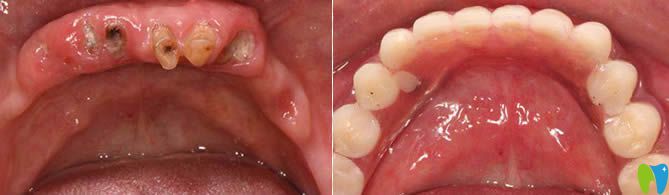

1、60歲老人全口種植牙前后對(duì)比及顧客反饋:

西安諾貝爾口腔李江院長(zhǎng)60歲老人全口種植牙前后對(duì)比<span style=

【顧客評(píng)價(jià)】:這家在我們當(dāng)?shù)厥莻€(gè)老品牌,很早都聽(tīng)說(shuō)比較出名,這次種牙也是我個(gè)咨詢(xún)的牙科。很正規(guī),環(huán)境也很舒適,我是早上檢查完,下午就完成了全口種植牙,感覺(jué)諾貝爾的種牙技術(shù)很靠譜,給醫(yī)生們點(diǎn)贊。